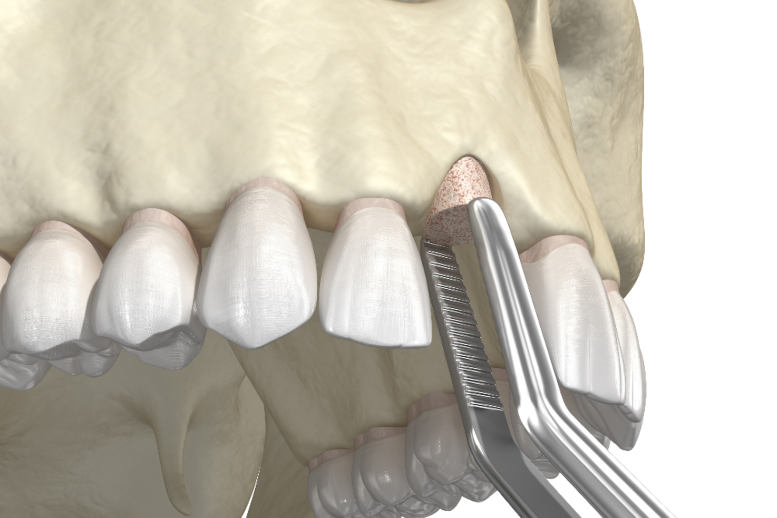

From www.alamy.com

3D render of dental bone grafting with membrane over white background Bone Graft Membrane Smell Soggy yellow stuff under the stitches (was gray the first couple days), but had a. Dental bone grafting is a procedure where we add bone or synthetic material to your jawbone. Can you tell me why i have that nasty taste and smell? Your success is based on numerous factors including how well your bone grafting was performed. Same smell. Bone Graft Membrane Smell.